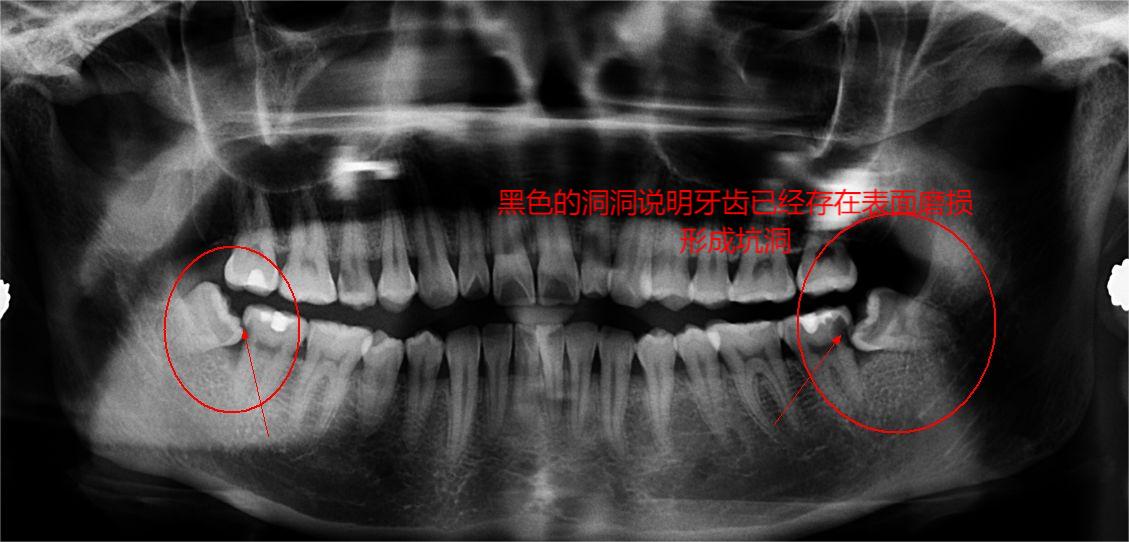

如果只是拍摄牙齿ct的话,很多私营牙科诊所会有赠送的拍ct的推广服务,但如果去公立医院该缴费的还是得缴费,各位可以注意一下身边的牙科诊所是否会有类似的促销活动,这个是我白蹭的牙片ct的截图,一共是3颗智齿:

很特殊的一共是3颗智齿

很明显,我并不是那种万中无一的天选智齿使用者,我甚至没法强行使用智齿...因为它们根本凑不出俩对,ct正面照看1号孤寡智齿好似正常,但实际情况是左右错位的,类似下图: